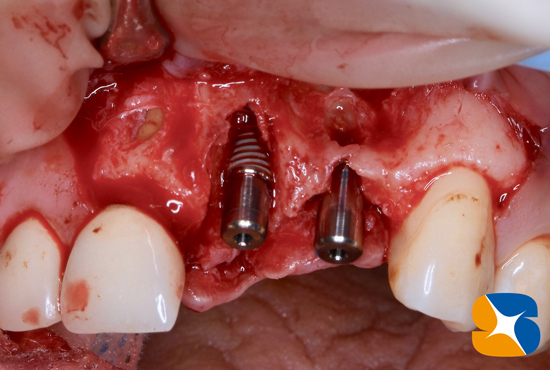

他社インプラントの撤去器材をお借りして、いざ手術開始。

(1)割れた根と(2)骨から突き抜けたインプラントを確認することが出来ました。

骨から突き抜けたインプラントを撤去

2本のNewインプラント、移植成功。

自己血液を使ってCGFを作り、人口の骨(βーTCP)を骨の欠落部にセッテングしたところです。

使用インプラント:(左)ノーベルバイオケア社製のパラレルCC 直径3.75㎜、長さ13㎜。

(右)アクティブ 直径3.0㎜、長さ13㎜。